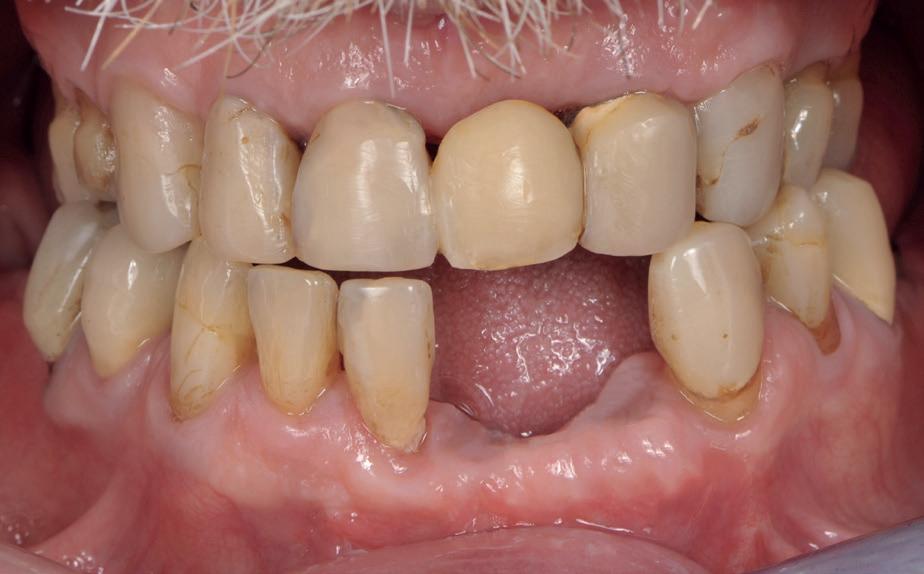

De patiënt, een 70-jarige man, had in het verleden tandheelkundige zorg ontvangen die zich kenmerkte door een ad hoc benadering. Er was geen sprake van een overkoepelend behandelplan of lange termijnvisie. De patiënt had naar eigen zeggen jarenlang niets

1. Studiofoto intake

aan zijn gebit gedaan behalve pappen en nathouden. Tandheelkundige zorg werd enkel verleend wanneer er zich een probleem voordeed (afbeelding 1, 3, 5).